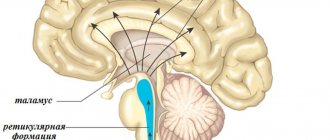

Until today, scientists have not been able to fully interpret what leads to manifestations of sleepwalking. But most scientists are inclined to believe that sleepwalking is a consequence of an imbalance in the functioning of parts of the brain.

This can be explained in more detail as follows: when a person falls asleep, his brain also rests, the departments fall into deep sleep. Then one of the departments “turns on” and begins to stay awake while the other department is fast asleep. Against this background, discord arises - the person is fast asleep, but his movements are active.